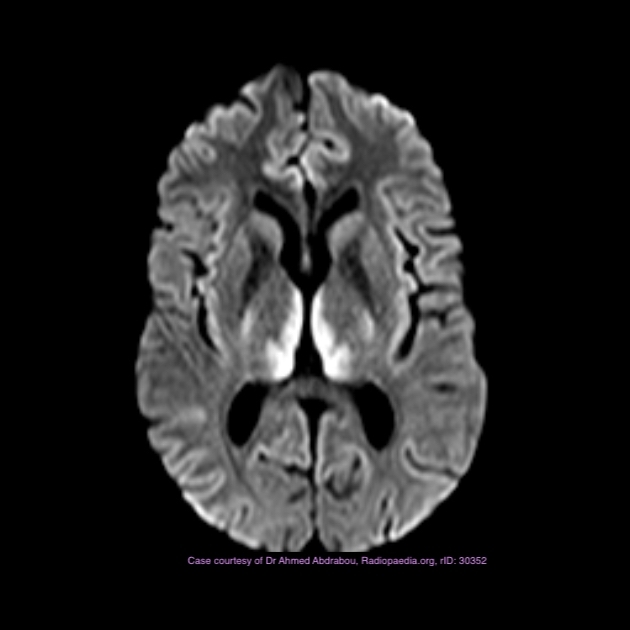

CNS capillary telangiectasia

Dr Daniel J Bell◉ and Dr Yuranga Weerakkody◉ et al.

CNS capillary telangiectasiae(s) are small, asymptomatic low flow vascular lesions of the brain.

Location

most occur in the pons, cerebellum and spinal cord

Radiographic features

Capillary telangiectasias are mostly located in the brainstem (especially the pons). They are more often solitary, but sometimes can be multiple. They have only become widely recognised in the radiology community following the introduction of MRI, as they are usually not seen on CT and DSA 2-5.

MRI

They appear as subtle lesions with no mass effect.

T1: typically iso to low signal compared with brain parenchyma

T2: normal or slightly increased signal intensity

FLAIR: normal or slightly increased signal intensity

T2*: low signal intensity

thought to be due to deoxyhaemoglobin from sluggish flow, not haemorrhage 2

T1 C+:

may demonstrate stippled enhancement

if large, can show branching/linear draining veins